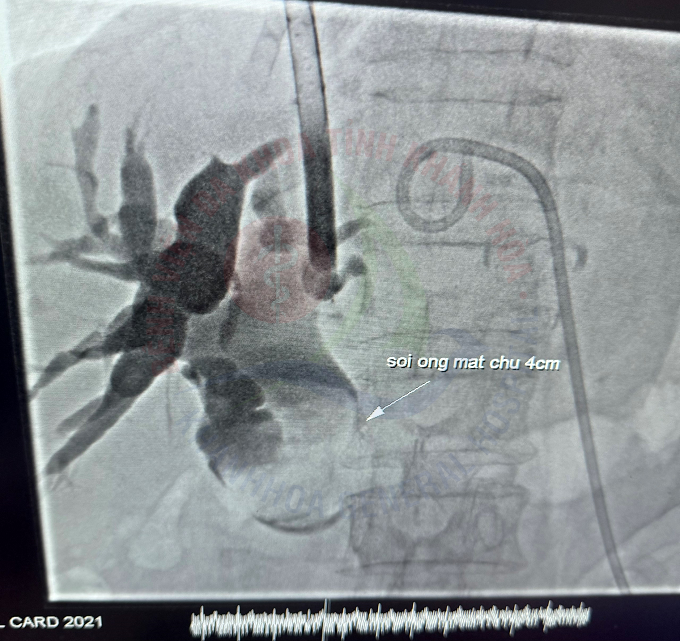

Một trường hợp đặc biệt vừa được các bác sĩ Bệnh viện Đa khoa tỉnh Khánh Hòa xử trí thành công. Đó là bệnh nhân T.T.D, 87 tuổi, trú tại huyện Vạn Ninh, nhập viện trong tình trạng nhiễm trùng đường mật nặng do sỏi ống mật chủ kích thước lớn, kèm theo sỏi trong gan và áp-xe đường mật gan trái.

Tuy nhiên, để xử lý dứt điểm nguyên nhân gây nhiễm trùng, cần phải loại bỏ sỏi đường mật. Với trường hợp đặc biệt này, các bác sĩ Bệnh viện phối hợp cùng chuyên gia tuyến trên lựa chọn phương pháp tán sỏi đường mật qua da bằng laser dưới hướng dẫn của hệ thống chụp mạch DSA đã được lựa chọn.

Chỉ một đường chọc nhỏ chỉ khoảng 5 mm trên thành bụng, các bác sĩ đã tiếp cận hệ thống đường mật, tiến hành tán sỏi bằng laser và lấy hết sỏi thành công. Ca can thiệp diễn ra thuận lợi, bệnh nhân tỉnh táo ngay sau thủ thuật, không đau nhiều, không để lại sẹo lớn, phục hồi tốt và xuất viện sau 1 tuần trong tình trạng ổn định.

Tán sỏi đường mật qua da bằng laser dưới hướng dẫn DSA là một kỹ thuật hiện đại, đánh dấu bước tiến lớn trong điều trị sỏi đường mật ít xâm lấn. Phương pháp này giúp can thiệp chính xác, giảm thiểu tỷ lệ chảy máu, biến chứng và rút ngắn thời gian hồi phục. Kỹ thuật có thể giải quyết các trường hợp sỏi ống mật chủ, sỏi trong gan.